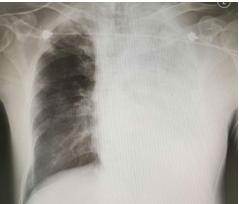

原本還有力氣哭鬧要回家的女童,經過安撫後漸漸安靜下來,才過沒多久,父母便發現女童呼吸狀況變得詭異、越來越喘,醫師當下急照X光檢查,震驚發現

女童病情急速惡化,因出現肺部積水緊急轉送加護病房,進行插管、呼吸器治療,但她的血壓卻開始不穩,使用強心劑維持血壓、心律等急救措施,儘管極力搶救仍回天乏術,送到醫院12小時左右就離開了!醫師張華倫無奈說明,